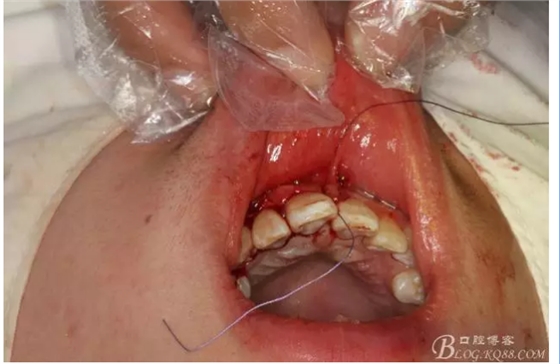

圖14.縫合水平切口

圖15.縫合垂直切口

圖16.縫合完畢,一周拆線。